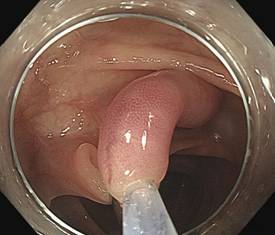

钛夹阻断血流,准备直接圈套,圈套切除,息肉离体以及创面

结肠黏膜-黏膜下拉长型息肉是由黏膜黏膜肌层、黏膜下层构成的细长有蒂型的大肠息肉,是一种相对少见的非肿瘤性病变,病因不明确。